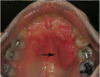

Which systemic disease manifests like this?

Crohn Disease

- Patients can also get angular cheilitis

- Above the Linear ulceration, can see a flap like structure which is the hyperplastic margin